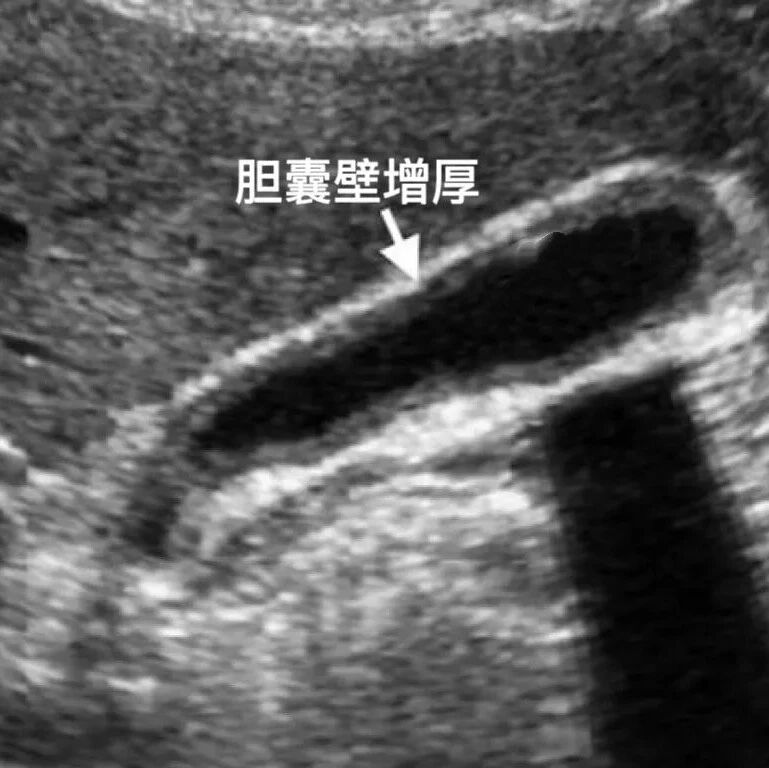

徐林|慢性无结石性胆囊炎(CAC)的特点和处理